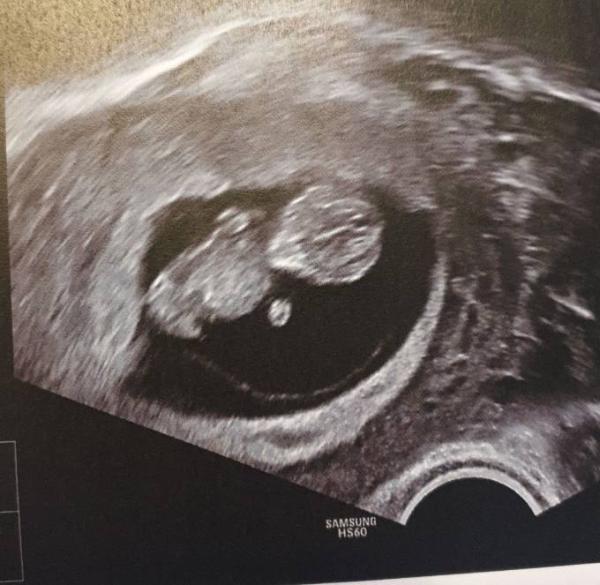

Hallo ihr Lieben, Ich durfte heute zum Schallen kommen, da es mir die letzten Tage gar nicht gut ging. Im Februar hatte ich einen MA bei 9+2. Heute bin ich 9+5... Ich habe mir so viele Gedanken gemacht, dass ich richtig richtig dolle Magenkrämpfe hatte. Die Beiträge der letzten Tage haben meine Angst glaube ich noch mehr geschürt. Sie war ganz lieb und verständnisvoll Und ich durfte einen 3,5 cm großen kleinen Menschen bewundern Wahnsinn wie die wachsen! Jetzt bin ich wirklich glücklich und entspannt. Die 10. SSW habe ich damit geschafft, das war ne harte Nuss Liebe Grüße Claudi

Bild zu Außerplanmäßiger FA-Besuch - Forum für Juli - Mamis